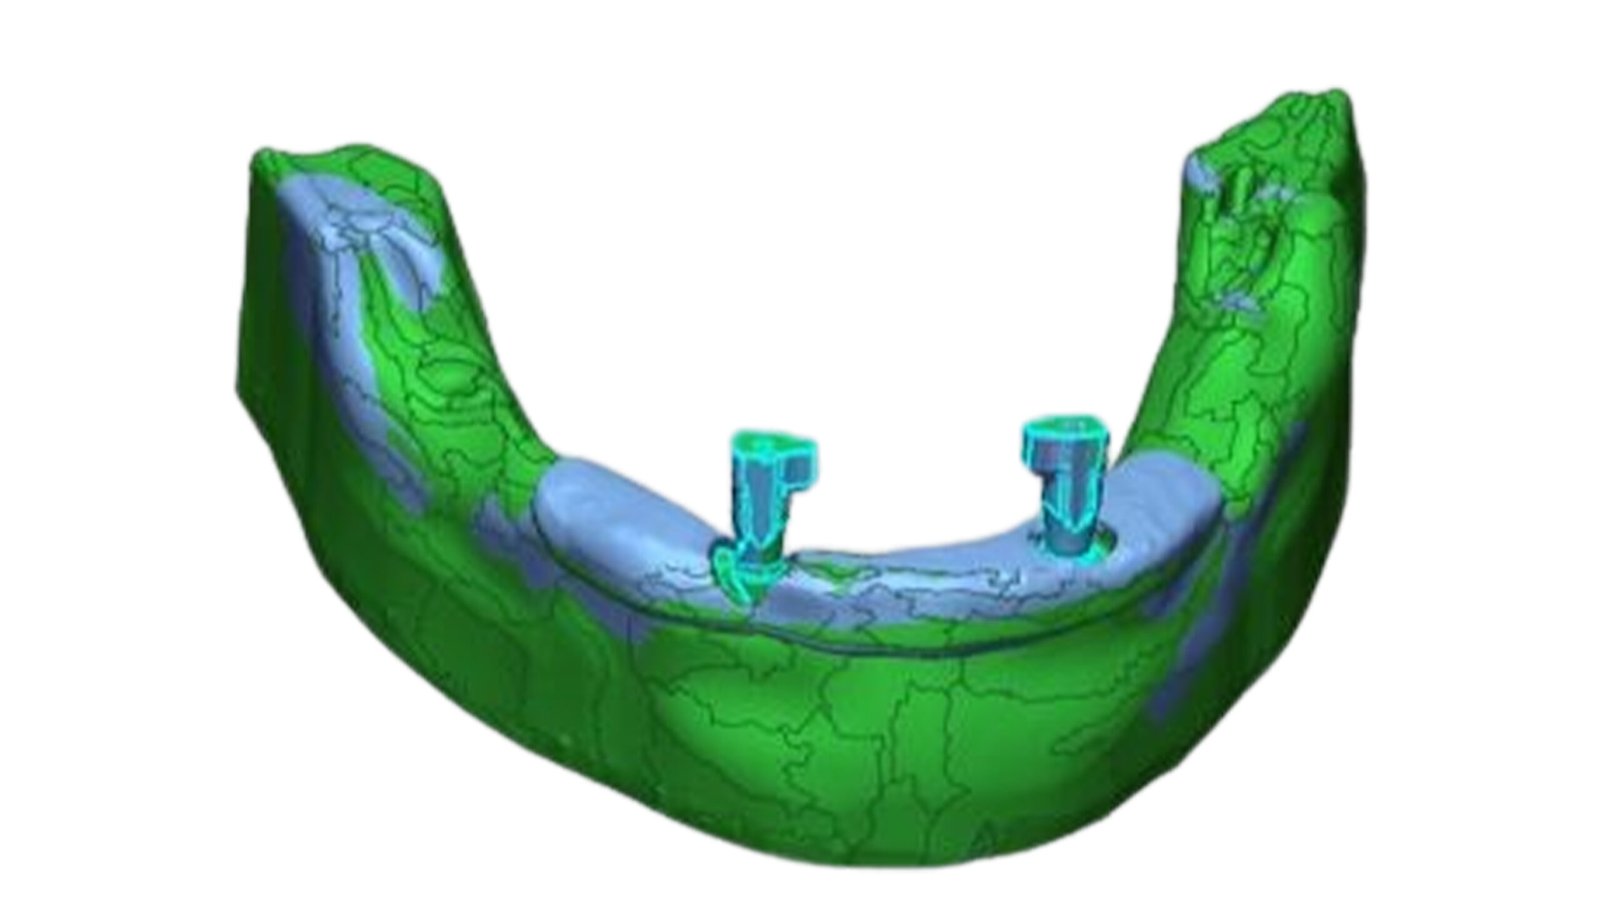

This section specializes in high-precision 3D deviation mapping to compare pre- and post-treatment anatomical or implant-related geometries. Using advanced superimposition and deviation algorithms, we quantify micro-level shifts, deformation zones, and structural discrepancies with sub-millimeter accuracy. These analyses support quality control, surgical verification, and design validation. The resulting deviation heat-maps provide clear, data-driven insights that enhance clinical decision-making and device optimization.